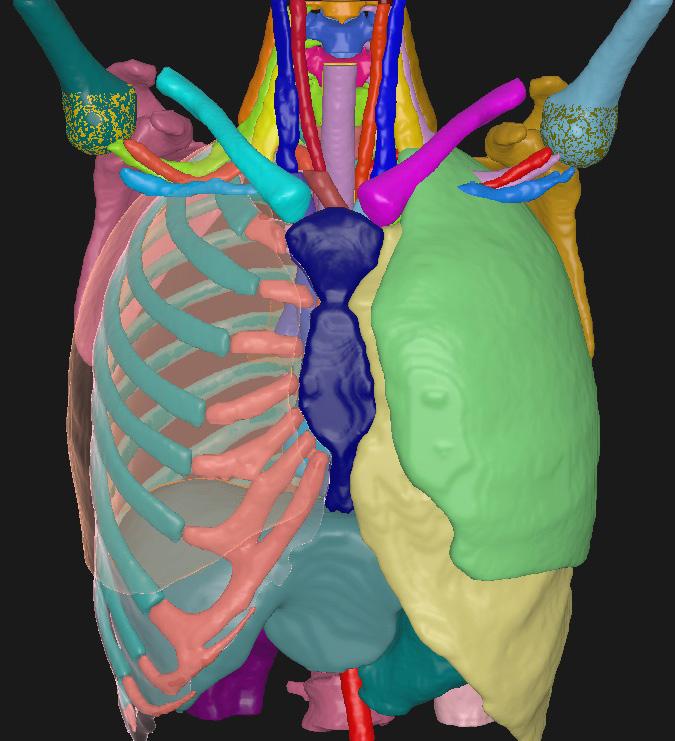

THORAX/ABDOMEN CT

STRUCTURES

BrachialPlex_L Esophagus

BrachialPlex_R Glnd_Thyroid

Bronchus_InterM Heart

Bronchus_Main _L Heart_Inferior_Left_PA

Musc_Scalene_Ant_L

Musc_Scalene_Ant_R

Musc_Scalene_Med_L

Musc_Scalene_Med_R

Bronchus_Main_R Humeral_Head_L IMPROVED Ribs_L NEW

Carina Humeral_Head_R IMPROVED Ribs_R NEW

Cartlg_Costal_L NEW Humerus_L NEW

Cartlg_Costal_R NEW Humerus_R NEW

Clavicle_L NEW Kidney_L

Clavicle_R NEW Kidney_R

CW_2cm_L NEW Liver

CW_2cm_R NEW Lung_L

CW_Anatomical_L NEW Lung_R

CW_Anatomical_R NEW

Pancreas

Scapula_L NEW

Scapula_R NEW

SpinalCanal

Spleen

Sternum

Stomach

Trachea